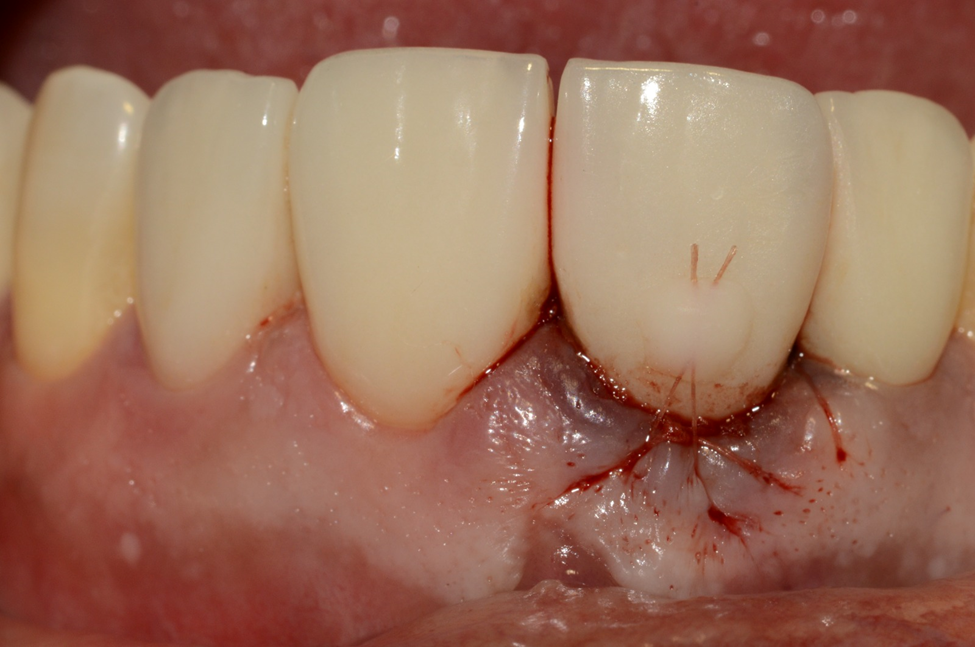

Como foi alcançado alto torque de inserção e travamento do implante (50 Ncm), foi realizada a carga imediata utilizando a própria coroa protética do elemento extraído (Figura 8), favorecendo o resultado estético e a manutenção do perfil de emergência peri-implantar. Uma sutura suspensória foi executada com o intuito de tracionar os tecidos moles em direção à coroa e prevenir recessão gengival (Figura 9).